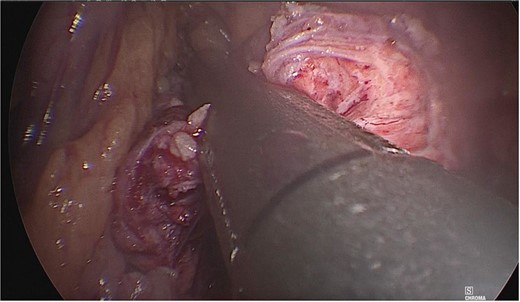

Dissection of the pancreas (body and tail) and splenic vascular structures (arteries and veins; Fig. 5). Intrapancreatic veins were identified. Dissection was performed with a harmonic scalpel of the pancreatic tissue of the vein, taking care not to disrupt it, and the dissection of vascular structures was completed, thus obtaining splenic preservation. The piece was removed, fibrin sealant was applied to the surgical site (Tisseel), and a drain was placed (Fig. 6). The patient had a satisfactory postoperative course and was discharged with a drain in place to be followed up in the outpatient clinic.

Dissection of the pancreas (body and tail) from splenic vascular structures (artery and vein).

Extraction of the anatomical piece preserving vascular structures.